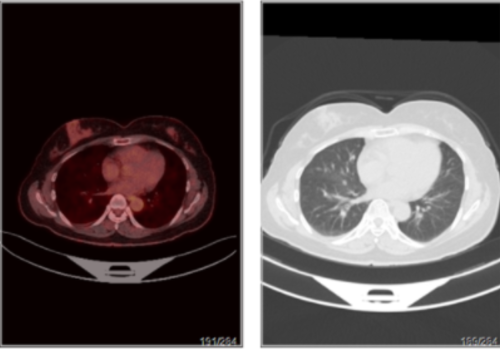

年 龄:64岁检查项目:全身临床诊断:肺癌治疗后显像剂(种类/剂量):18F-FDG/9.4mCi简关病史:2019.10.14于肺科医院行VATS左全肺切除术,肺门部肿块,4*3*2. 5cm, 病理为鳞癌(非角化性),胸膜、神经浸润及脉管内癌栓均未见;术前化疗3 程,术后继续化疗4程,无放疗,末次治疗时间为2020. 02. 25,术后一直声音 嘶哑,最近一次复查2020. 06.18胸部CT提示:左肺术后改变伴包裹性积液,右 肺多发结节